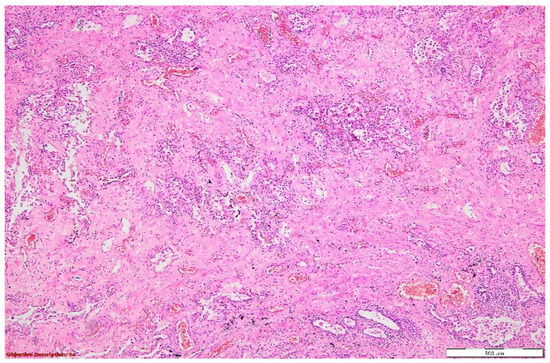

Figure 8. Lung parenchyma with distended alveoli by abundant inflammatory elements composed mainly of neutrophils; thickened interstitial space due to the hyperemia and moderate inflammation. HE, 100×.